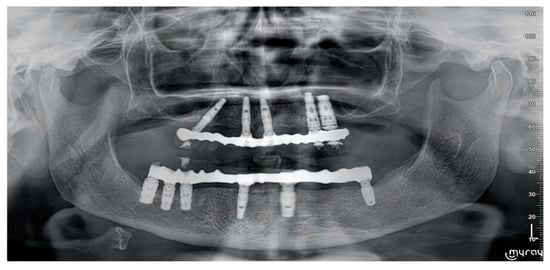

- Marginal bone levels were measured as the distance between the implant platform to the first bone to implant contact. Mean values of mesial and distal measurements were calculated for each implant. Marginal bone level was measured on digital periapical radiographic images obtained by parallel technique with Rinn’s film holder (Rinn XCP, Dentsply, Elgin, IL, USA) taken at definitive implant loading (baseline) and then one year after. All radiographs were analyzed through a dedicate software (DFW2.8 for Windows, Soredex, Tuuka, Finland), calibrated for each image using the known distance between two consecutive threads. The difference between baseline and last follow-up was taken as marginal bone loss. One dentist at each center, not previously involved in this study, performed every radiographic measurement.

| Marginal bone | 0.05 ± 0.07 | 0.32 ± 0.2 | 0.27 ± 0.14 |